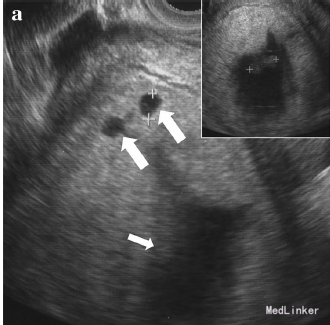

31岁女性,G2,孕10周,因诊断OHSS合并卵巢肿块就诊

hCG 390000 IU/L 超声提示胎盘上有数个囊性肿块,胎儿无胎心 超声还提示双侧卵巢囊性肿块

诊断为OHSS合并葡萄胎 行诊断性刮宫,提示葡萄胎 术后hCG 9830 IU/L OHSS症状愈加明显 患者卵巢增大、出现胸水、腹水,体重增加 术后17天症状缓解 1月后卵巢恢复正常大小 刮宫后20周hCG恢复正常